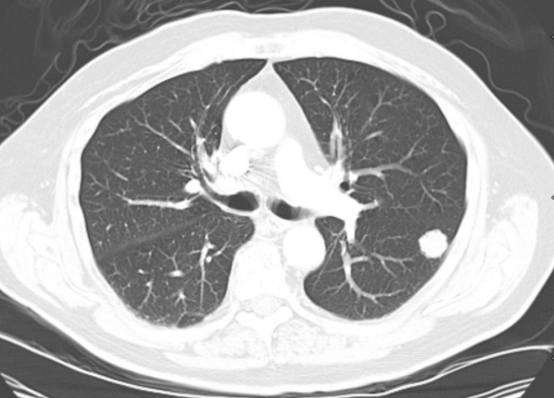

去年检查的时候就查出肺结节的问题 , 听到自己肺内长了东西 , 这吓坏了他 , 当即表示要戒烟 , 医生说戒烟是最好的 , 看了胡先生的检查单 , 医生说道 , 这个肺结节大概率是良性结节 , 癌变的可能性非常低 , 但是胡先生很害怕 , 整日里胆战心惊的 。

肺结节这种疾病近些年来变得越来越普遍 , 然而多数肺结节是良性结节 , 其中恶化的比例不到5% , 因此即使查出肺结节的问题 , 也不再整天怨天尤人 , 避免过度恐慌 。 生活中多注意 , 慢慢结节是会消散的 。

1、结节直径小于5毫米

结节直径小于5毫米 , 这属于小结节 , 其中良性的概率高达95% , 但是同时要注意若是结节直径超过1厘米 , 要尽快前往医院进行检查 , 同时确定下一步 。

2、异常结节形态清晰

若是肺内结节边界清晰 , 没有毛刺 , 密度均匀 , 这大概率是良性结节 , 因此不必过于惊慌 。

3、没有出现胸膜牵拉问题

若是身体出现胸膜牵拉的问题 , 建议做进一步的穿刺活检 , 但是若是没有这种情况 , 不必过于惊慌 。

4、结节稳定

若是结节长时间稳定 , 没有增大的趋势 , 说明结节属于良性结节 。